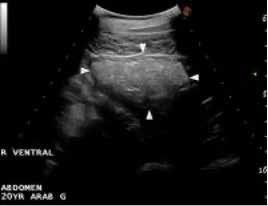

The radiographs detected no enteroliths or sand in his system, so he was referred for an abdominal ultrasound with the Large Animal Ultrasound Service. There Betsy Vaughan, DVM, department vicechair health sciences professor of clinical, observed a long segment of severely distended and fluid-filled small intestine with poor motility. This appearance was highly suggestive of a small intestinal obstruction, although the cause of the obstruction could not be seen, so Dr. Vaughan recommended exploratory surgery.

Transverse ultrasound image of Oskie’s severely distended small intestine before surgery. Transverse ultrasound image of Oskie’s normal small intestine after surgery. Images courtesy of UC Davis